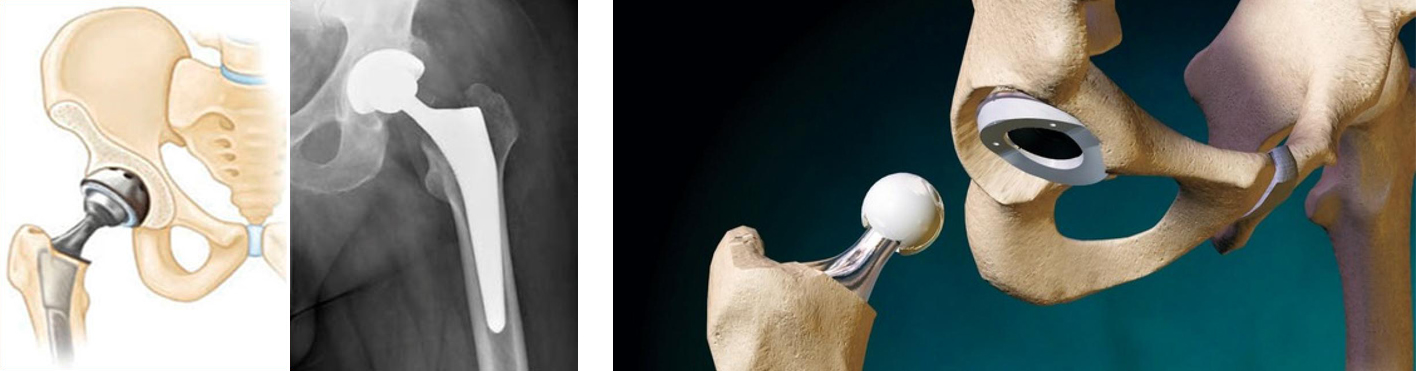

Некроз тазобедренного сустава: Фотографии и особенности лечения

Раздел: Необычные решения